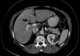

Diffuse infiltrating liver metastasis